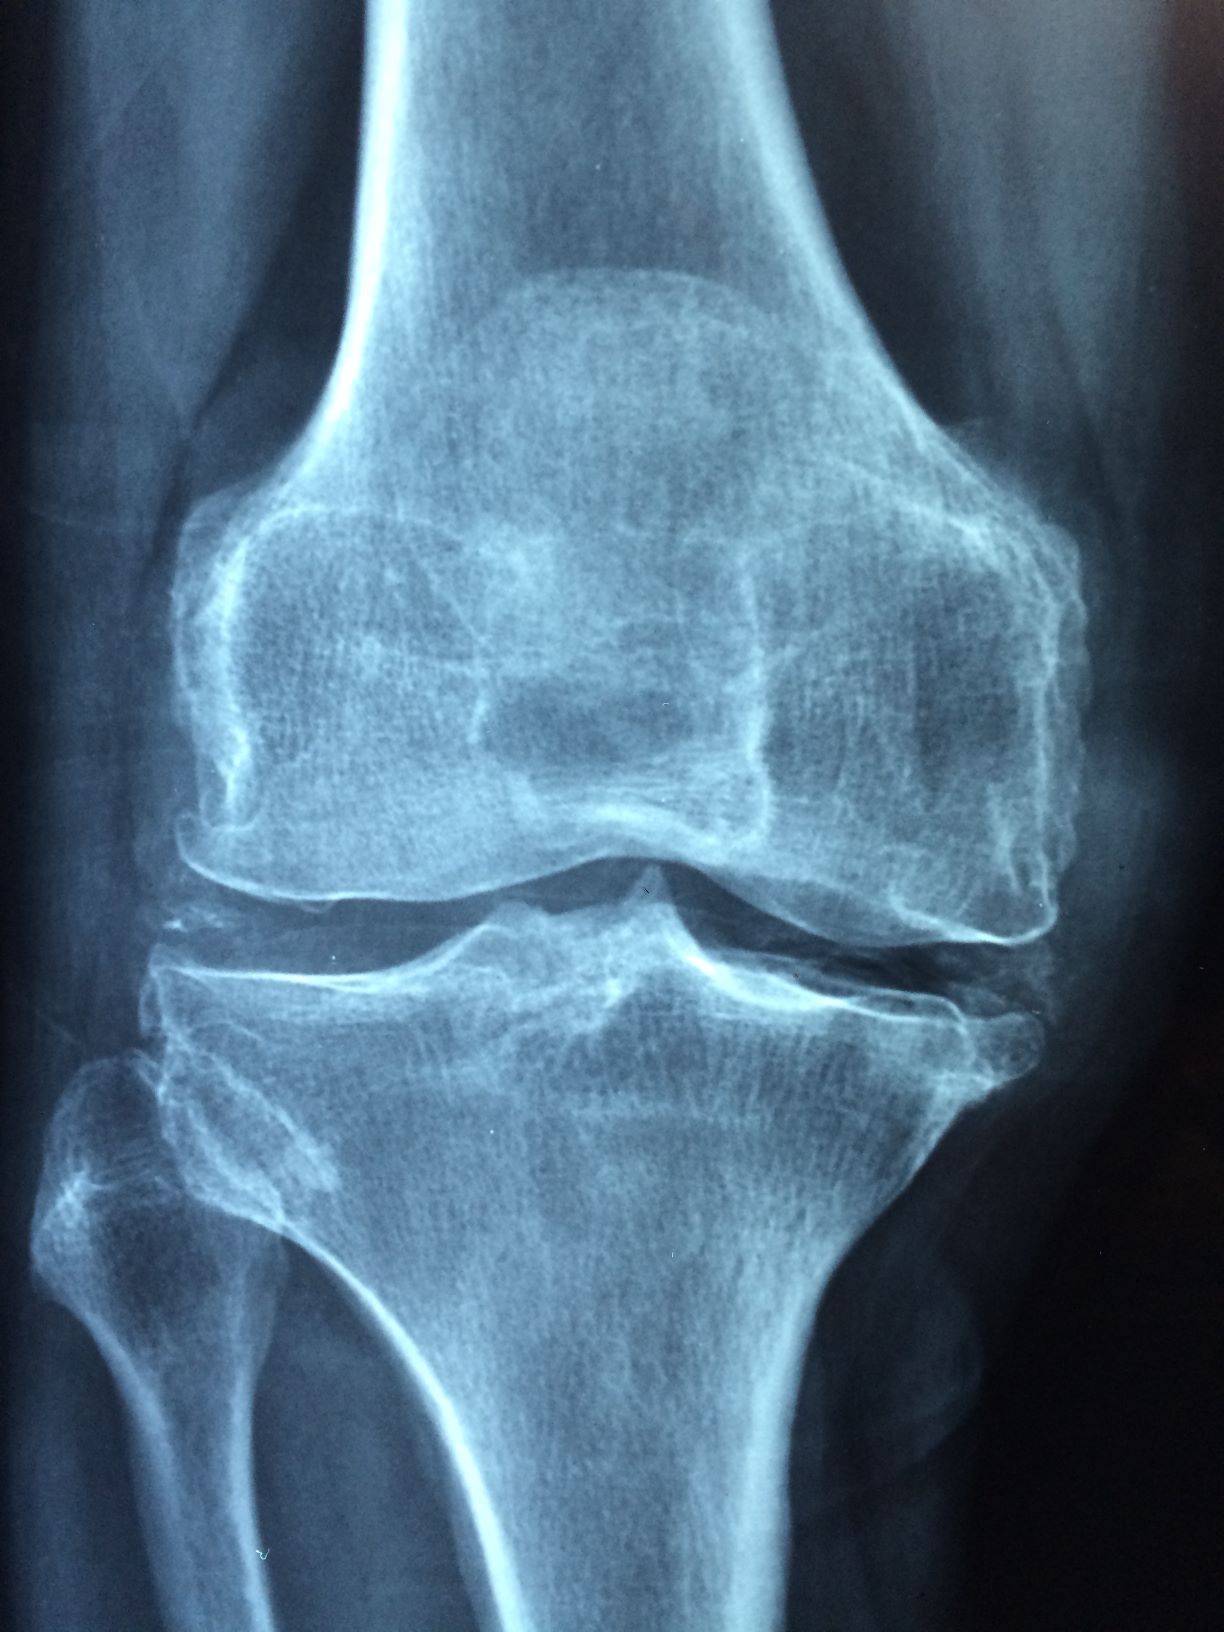

Starnutie populácie vyvoláva vysoký dopyt po liekoch a procedúrach na regeneráciu kostí. Čoraz častejšie sú pritom biomateriály používané na podporu tejto liečby navrhované tak, aby boli imunomodulačné – t. j. aby ovplyvňovali zápalovú odpoveď tela. Robia to tým, že podporujú makrofágy – druh bielych krviniek, ktoré obklopujú a zabíjajú mikroorganizmy, aby na seba zobrali nové úlohy založené na signáloch a stimuloch v ich mikroprostredí. Tento prístup sa ukázal ako efektívny pri vytváraní novej kosti a podpore toho, aby existujúce kosti prijali umelé implantáty. Magnézium je minerál, ktorý nielenže pomáha udržiavať normálne nervové a svalové funkcie, čo je samo osebe dôležité, ale tiež podporuje zdravý imunitný systém a pomáha kostiam udržiavať si svoju silu. Bežne sa preto podáva pacientom ako výživový doplnok.

V nedávnej štúdii publikovanej v časopise Bioactive Materials skupina výskumníkov z Hongkongu a pevninskej Číny otestovala nový imunomodulačný prístup, ktorý nahrádza magnéziový doplnok injekciou priamo do postihnutej kosti. Injekcia obsahuje špeciálne vyrobené polymérové mikrosféry, ktoré kontrolujú uvoľňovanie iónov magnézia. Podľa jedného z autorov štúdie, profesora ortopédie a traumatológie na Hongkonskej univerzite Kelvina Yeunga, tím testoval svoju hypotézu použitím dvoch rozličných zvieracích modelov. Jednému sme injekčne podali mikrosféry obsahujúce ióny magnézia, druhému mikrosféry bez magnézia. Počas nasledujúcich dvoch týždňov sa v prvej skupine dala pozorovať rýchlejšia regenerácia kostí.

Podľa K. Yeunga je jednou z výhod magnézia podpora imunitného a kostrového systému v tom, aby pracovali spoločne, čím sa zlepšuje in situ hojenie. Vývoj biomateriálu na opravu kostí zvyčajne zahŕňa priamu aktiváciu osteoprogenitorových buniek – kmeňových buniek nachádzajúcich sa v kosti, ktoré hrajú kľúčovú úlohu v jej oprave a raste. No konverzácia, ktorá prebieha medzi kostrovým a imunitným systémom počas procesu hojenia kosti, bola často prehliadaná.